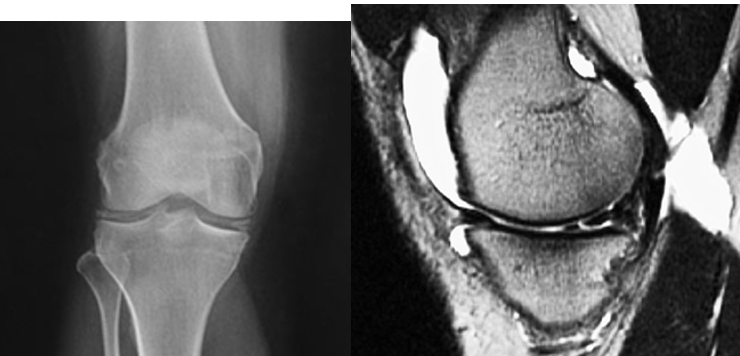

19

Q

Degenerative Joint Disease/Arthritis Imaging

• XR:

• Recommended views

• Weight-______ views of affected joint

• Optional views

• S______ view

• _ _ view in 30 degrees of flexion

• Look for:

• Joint _____ narrowing

• Osteo_____

• Subchondral s______

• Subchondral c_____

• MRI: ______ the urge, especially in advanced disease

A

• Weight-bearing views of affected joint

• Sunrise view

• PA view in 30 degrees of flexion

• Joint space narrowing

• Osteophytes

• Subchondral sclerosis

• Subchondral cysts

• MRI: Resist the urge, especially in advanced disease